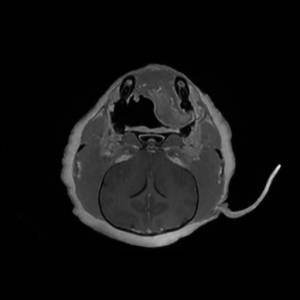

Main Gallery

Playing with a photo gallery function. It is possible to have multiple galleries, each within a namespace.